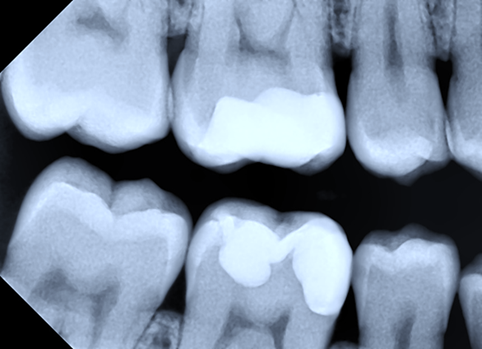

|

Fig. 2 Bitewing radiography. Mesial restoration (convex emergence profile) in tooth 16 with intact adjacent tooth. Mesial restoration (convex emergence profile) in tooth 46 with intact adjacent tooth. |

|

Fig. 3 Bitewing radiography. Distal restorations in teeth 24, 25, 26 with adjacent teeth with proximal restorations. |